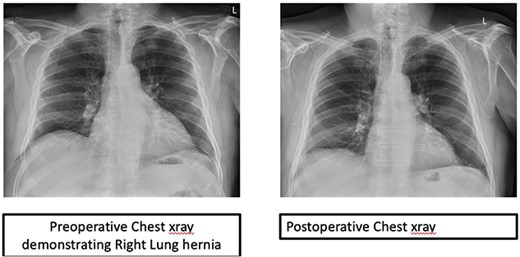

The patient had an uneventful recovery and remains asymptomatic with no recurrence after 6 months (Fig. 3).